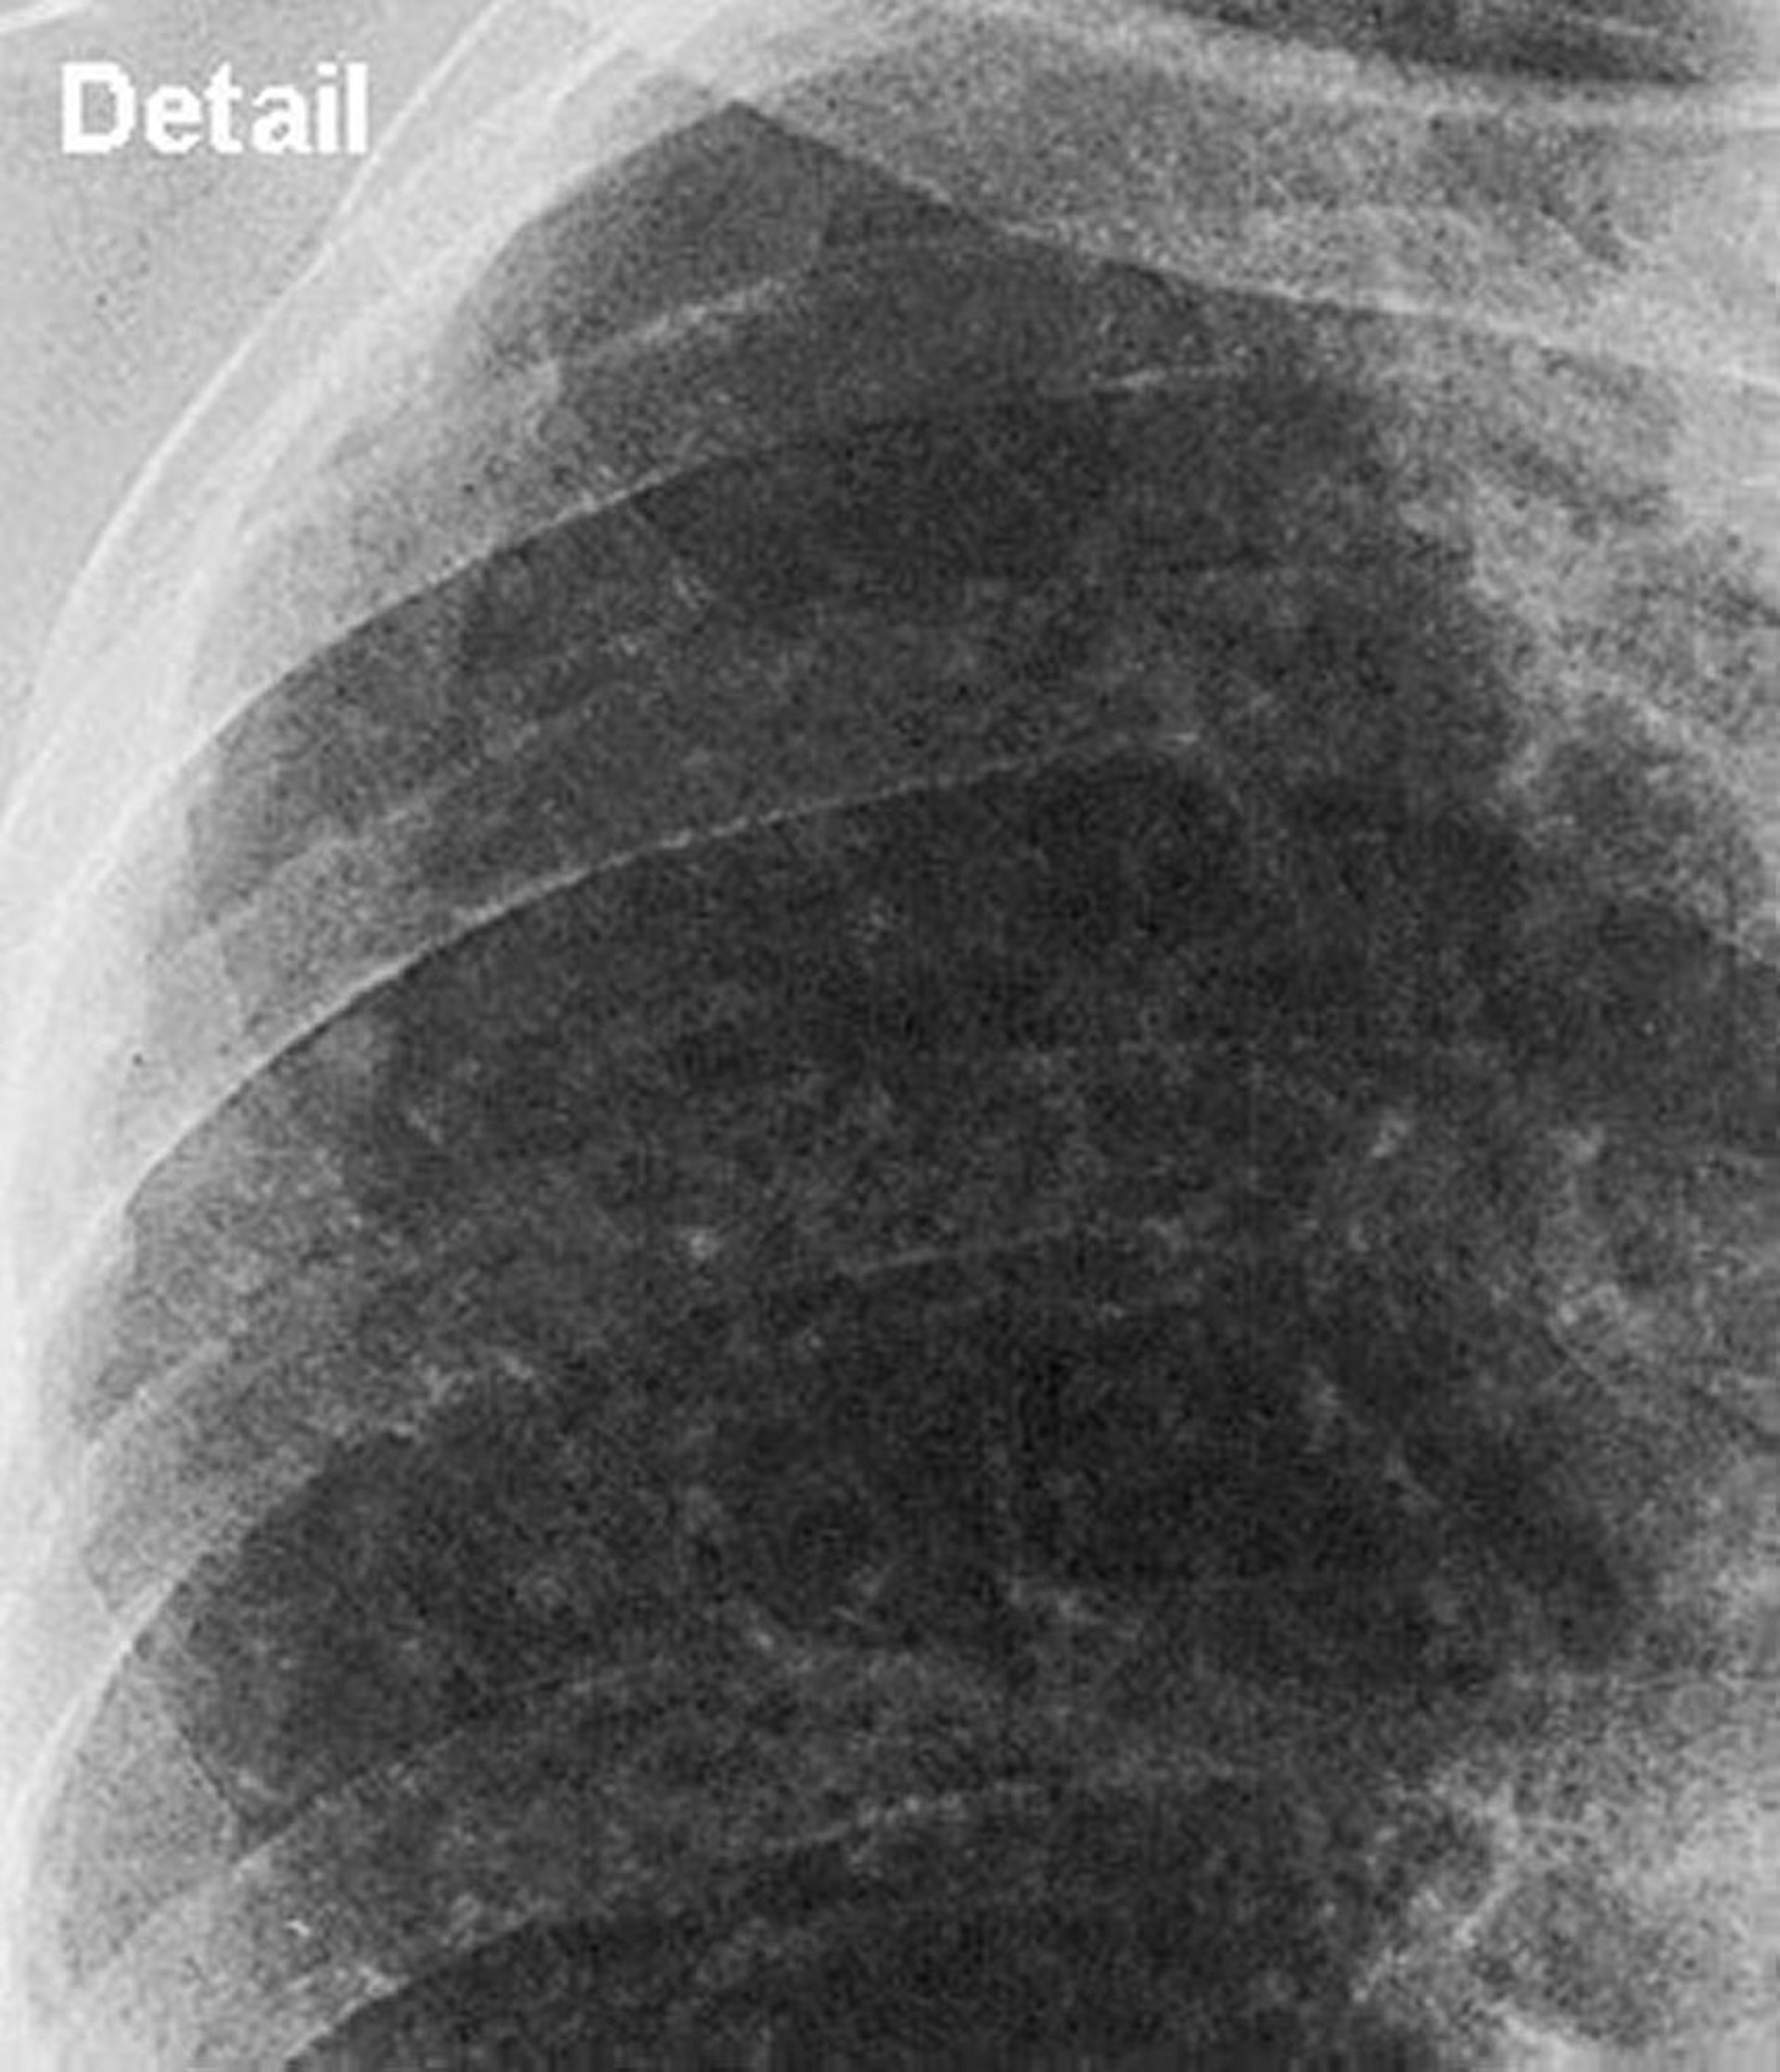

Silicose, simple (champ pulmonaire supérieur)

Gros plan sur le champ pulmonaire supérieur dans la silicose simple.

Image courtoisie de David W. Cugell, MD.